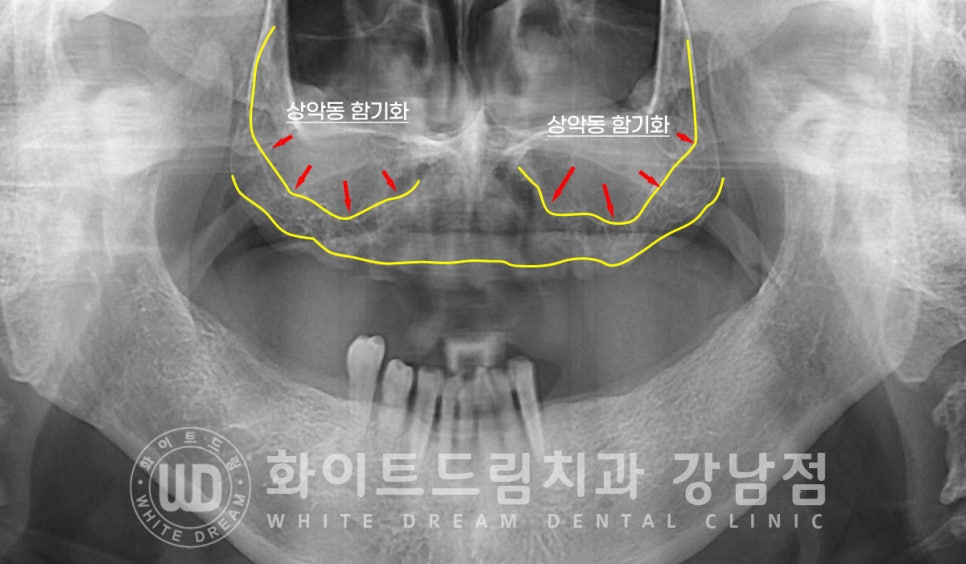

환자분은 발치한지 얼마 되지 않으셨음에도 함기화가 어느 정도 진행되고 있어

상악동을 살짝 들어 올린 후 모자란 잇몸뼈를 보강하는

상악동 거상술을 진행해야 할 정도로 잇몸뼈가 얇은 상태였답니다.

잇몸뼈의 길이가 임플란트의 길이보다 짧게 남아있는 상태여서

많은 양의 뼈이식이 필요했기에

이럴 때 진행하는 상악동 거상술 방법, 측면부 접근법(lateral)을 이용하여 수술을 진행하기로 했습니다.

이 lateral은 잇몸뼈의 옆쪽을 잘라 작은 창문을 만들고 이 창문을 통해 뼈이식재를

식립하는 방법입니다.

많은 양의 뼈를 생성할 수 있다는 장점이 있지만, 수술의 난이도가 높습니다.

그리고 수술 후 통증과 붓기가 발생한다는 단점을 가지고 있습니다만

수술을 진행하는 의료진이 수술 부위를 직접 눈으로 보고 진행하기에

경험이 많은 의료진이 진행한다면 예후가 아주 좋은 방법이기도 하답니다.

어금니 2개 이상을 상실하신 분들은 뼈 흡수가 많이 진행되었기에

대부분 lateral을 이용하여 많이 진행합니다.